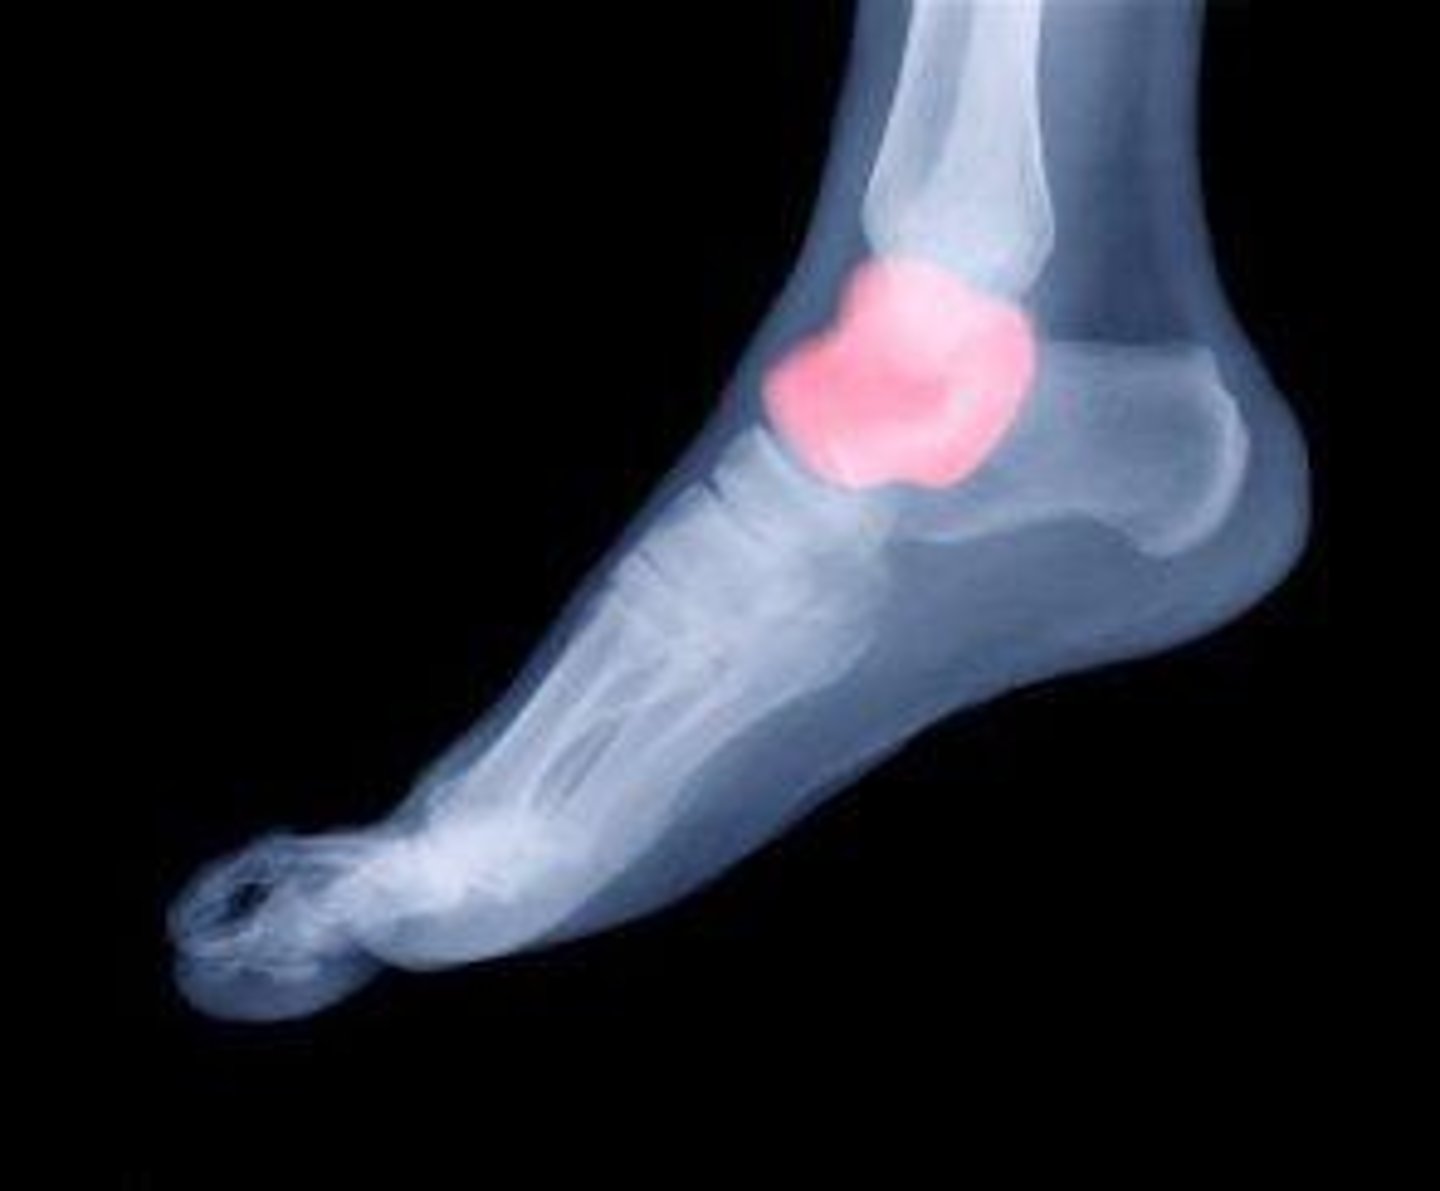

Calcaneus

What is the term of the bones highlighted in green?

Talus

What is the term of the bones highlighted in pink?